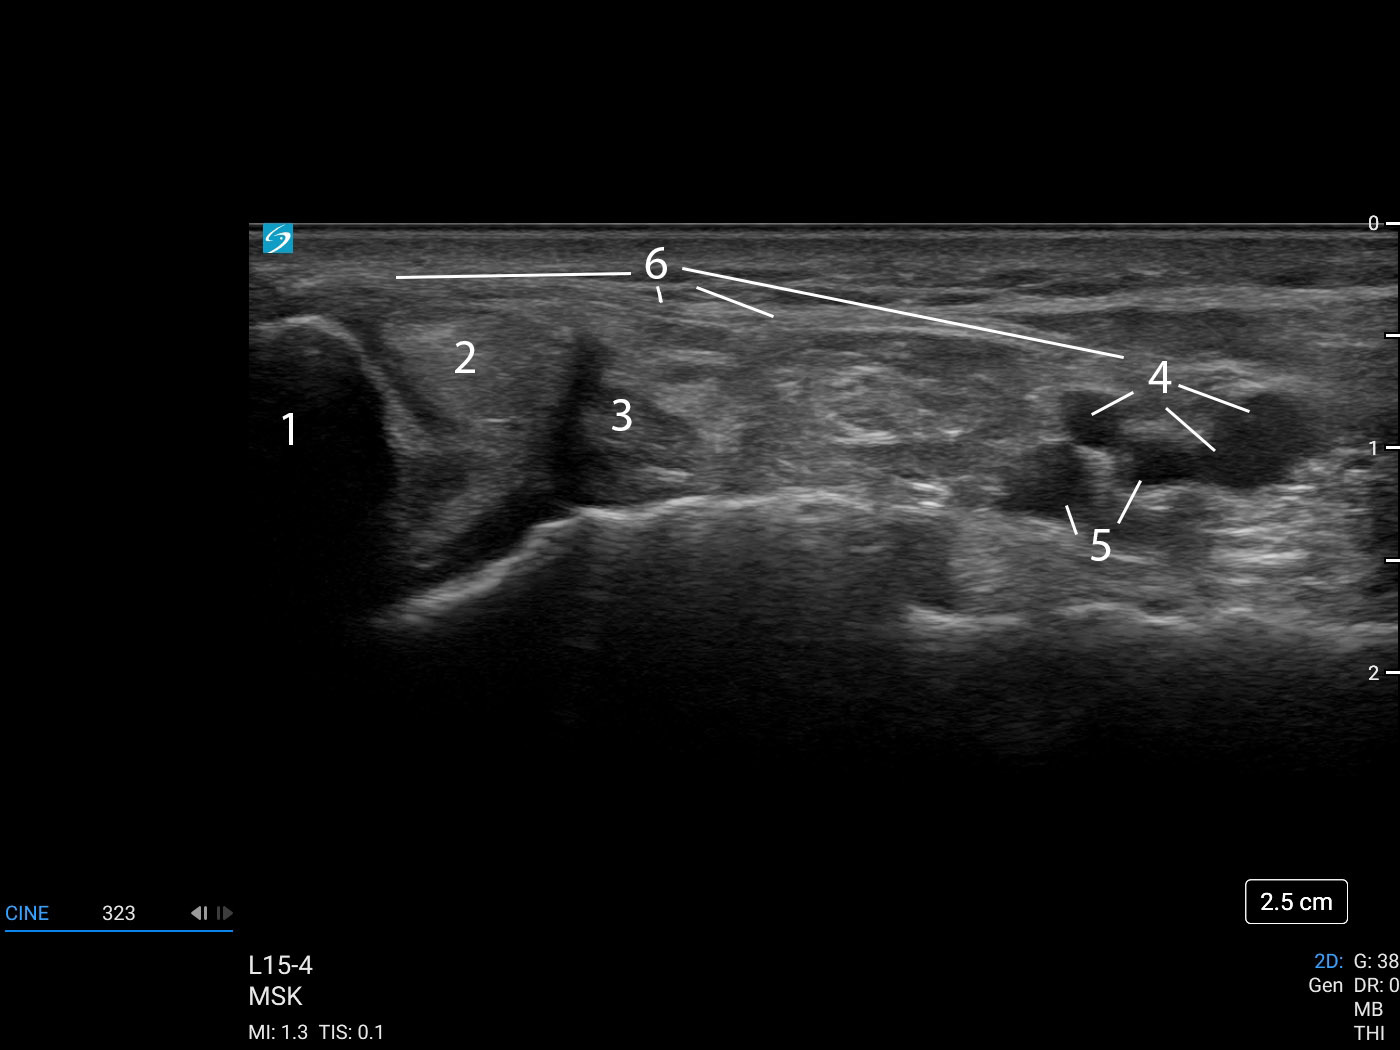

1. Medial Malleolus

2. Tibialis Posterior Tendon

3. Flexor Digitorum Longus Tendon

4. Posterior Tibial Veins (compressible)

5. Posterior Tibial Artery (pulsatile)

6. Flexor Retinaculum